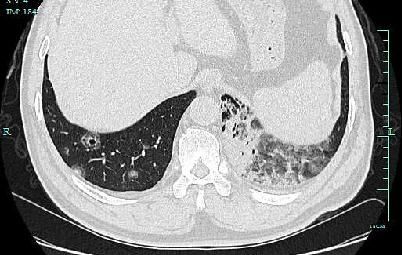

遗憾的是,由于张伯双肺内多发病灶,已经无法用手术切除。呼吸内科专家团队为他制定了化疗方案,目前张伯已接受化疗治疗,通过CT复查显示病灶明显缩小,咳血症状也明显好转。

文章插图

经过化疗后,张伯病灶明显缩小